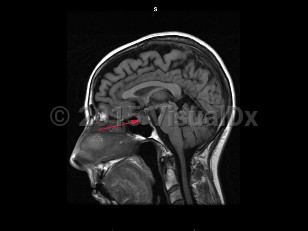

A craniopharyngioma is a brain tumor arising from pituitary embryonic tissue. It is typically suprasellar and has solid and cystic components. Age of onset can occur in childhood (about age 5-15) or adulthood (about age 50-70). There are adamantinomatous, papillary, and mixed types. Adamantinomatous tumors are more common in children and papillary tumors are more common in adults. A Rathke cleft cyst may develop from Rathke pouch if the pouch does not close normally.

Craniopharyngiomas are usually slow growing, and symptoms arise from compression of surrounding structures or increased intracranial pressure. Presenting symptoms include visual loss (most commonly superior temporal quadrantanopsia), headache, hormonal imbalances leading to delayed puberty in children, amenorrhea, hypersomnia, diabetes insipidus, and/or decreased libido. These tumors are usually benign with a good prognosis, but often recur when resection is incomplete.